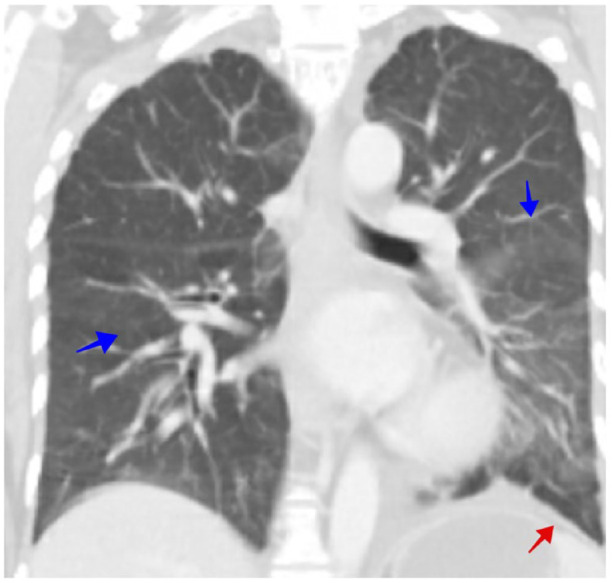

SARS-CoV-2 infection induces myocardiopathy in 19% of severe cases, with a mortality rate of up to 51%. The mainstay of treatment is supportive care, steroids, and tocilizumab (anti-IL-6). This is a case of a 43-year-old woman diagnosed with hormone-positive breast cancer with lung metastasis and pulmonary lymphangitis carcinomatosis (PLC). Her baseline cardiac function was within normal limits. She presented to the emergency department with respiratory distress. Chest CT showed multiple bilateral ground-glass opacities consistent with COVID-19 pneumonia and confirmed by COVID-19-PCR nasal swab. Her condition deteriorated, and she was urgently admitted to the intensive care unit with evidence of a cytokine storm. She was started on tocilizumab, dexamethasone, and meropenem. Echocardiogram (echo) showed a severely reduced ejection fraction with severe global hypokinesis. A second dose of tocilizumab was given, and the dexamethasone dose was increased. Fortunately, the patient had significant clinical and biochemical improvement and regained her normal cardiac function. In conclusion, dexamethasone and tocilizumab could be promising aids in treating cardiomyopathy secondary to SARS-CoV-2 infection.

Abstract Image